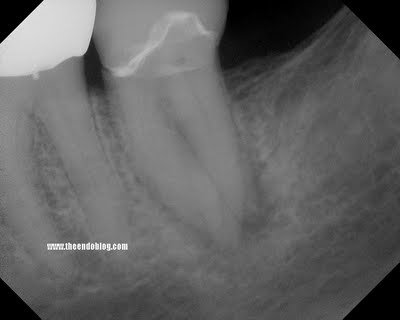

This patient came to SSE for emergency treatment. #18 DX: Necrotic pulp w/ Symptomatic Apical Periodontitis. RCT initiated. 3 canals located, however a 4th distal canal is not found. 2 distal roots are apparent the pre-op film. The ML, MB and a distal canal are located. The distal is opened looking for the 4th canal. After 20-30 minutes of searching for 4th canal, the patient is re-appointed for 2 step treatment.

With these images, the 4th canal is easily located within minutes of opening the tooth.